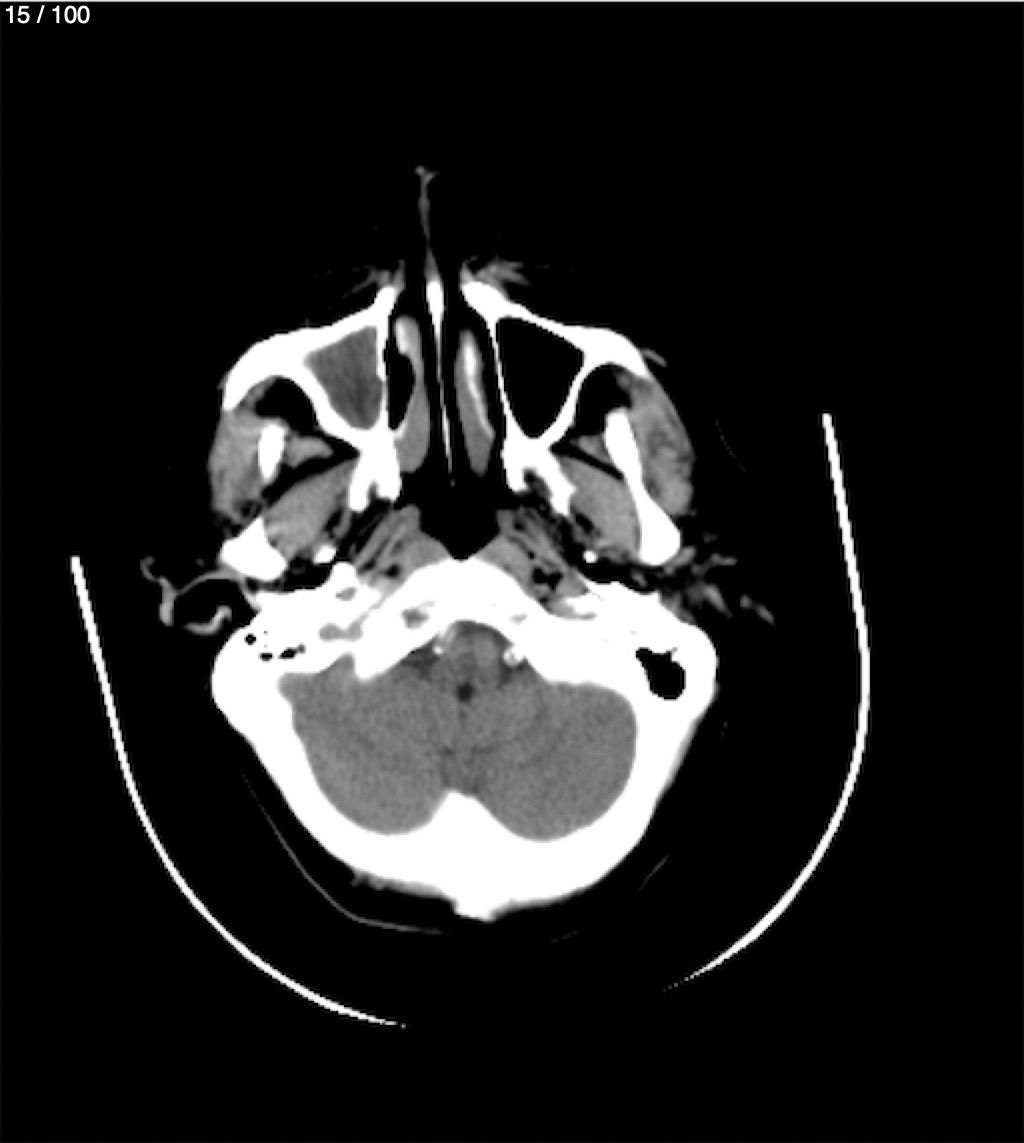

Valentin Perez Gomez 69A - T.C Craneo